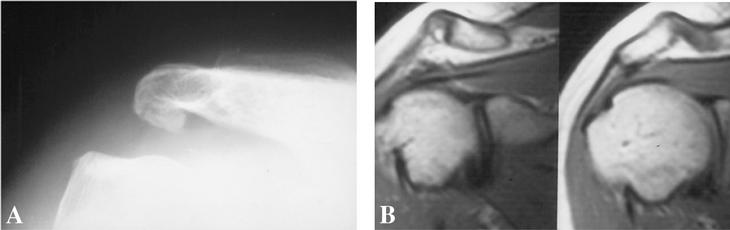

Las causas extrínsecas del atrapamiento del espacio subacromial se deben a anomalías en la bóveda acromial y a la articulación acromioclavicular. Bigliani y Morrison4 describieron en cadáveres tres tipos de acromion: el tipo I o plano, el tipo II o curvo y el III o en forma de gancho. Sólo el 39% de las articulaciones analizadas presentaron un acromion tipo III, si bien el 70% de éstos presentaban una lesión del manguito rotador (fig. 2). Por su parte, Gerber et al10 relacionaron el síndrome subacromial crónico con el atrapamiento subcoracoideo en relación con el papel de la apófisis coracoides y en sus tres formas, idiopática, yatrogénica y traumática.

Figura 2. Correlación radiográfica y de resonancia magnética (RM) de un acromion tipo III.